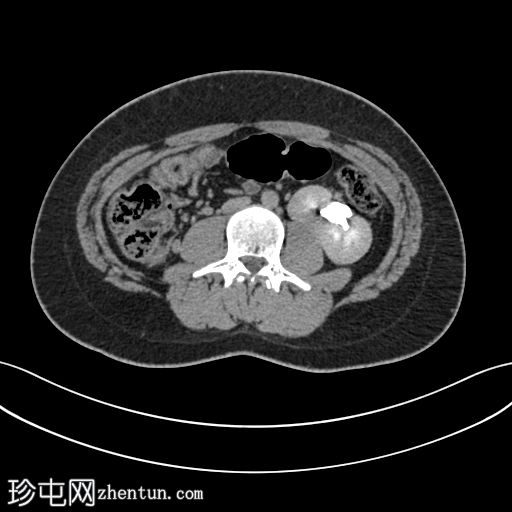

轴位

轴位CT图像显示双肾位于腹部左侧,肾实质融合,符合交叉融合性肾异位。延迟期图像证实双侧输尿管均正常开口于膀胱,右侧输尿管跨越中线开口于右侧膀胱输尿管连接处。